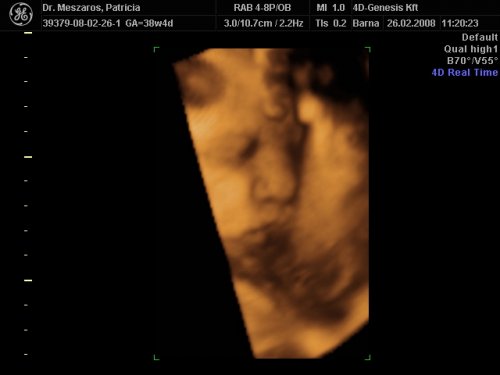

[quote="mpatr"][ írta:mpatrb]Nici, a felvétel élessége és sikerültsége sok mindentől függ.

A profi gépen túl a profi és türelmes szonográfus, a lepény és baba helyzete (mellső fali lepénynél kicsit nehezebb az ügy, meg a babák is imádnak belebújkálni a lepénybe), a magzatvíz mennyisége, a mama hasfalának zsírrétege (mennyire dagi anyuci) szóval ezek (biztos van még) min-mind befolyásolják a felvétel minőségét.

Nekem sikerült ugyanarról a gyerkőcről aki a pocimban van nagyon tuti és nagyon sz..r képet is készíteni ugyanazzal a géppel.

Érdemes többször próbálkozni.